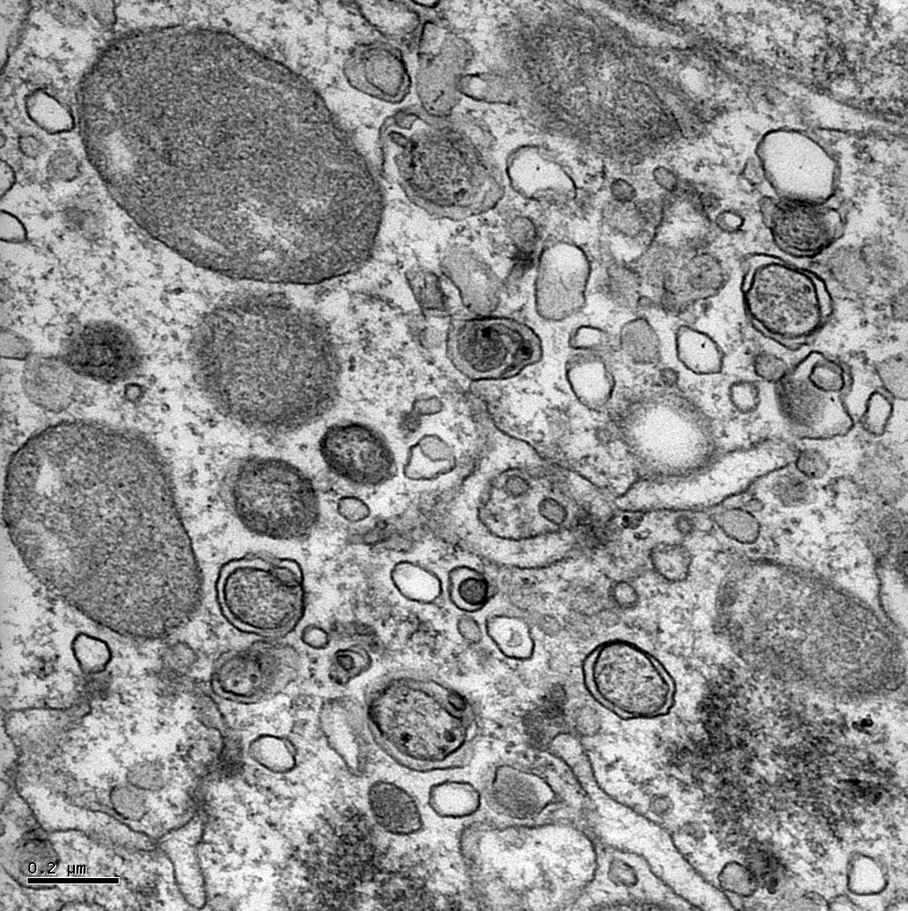

Exploring the boundaries of viral research

Exploring the boundaries of viral research